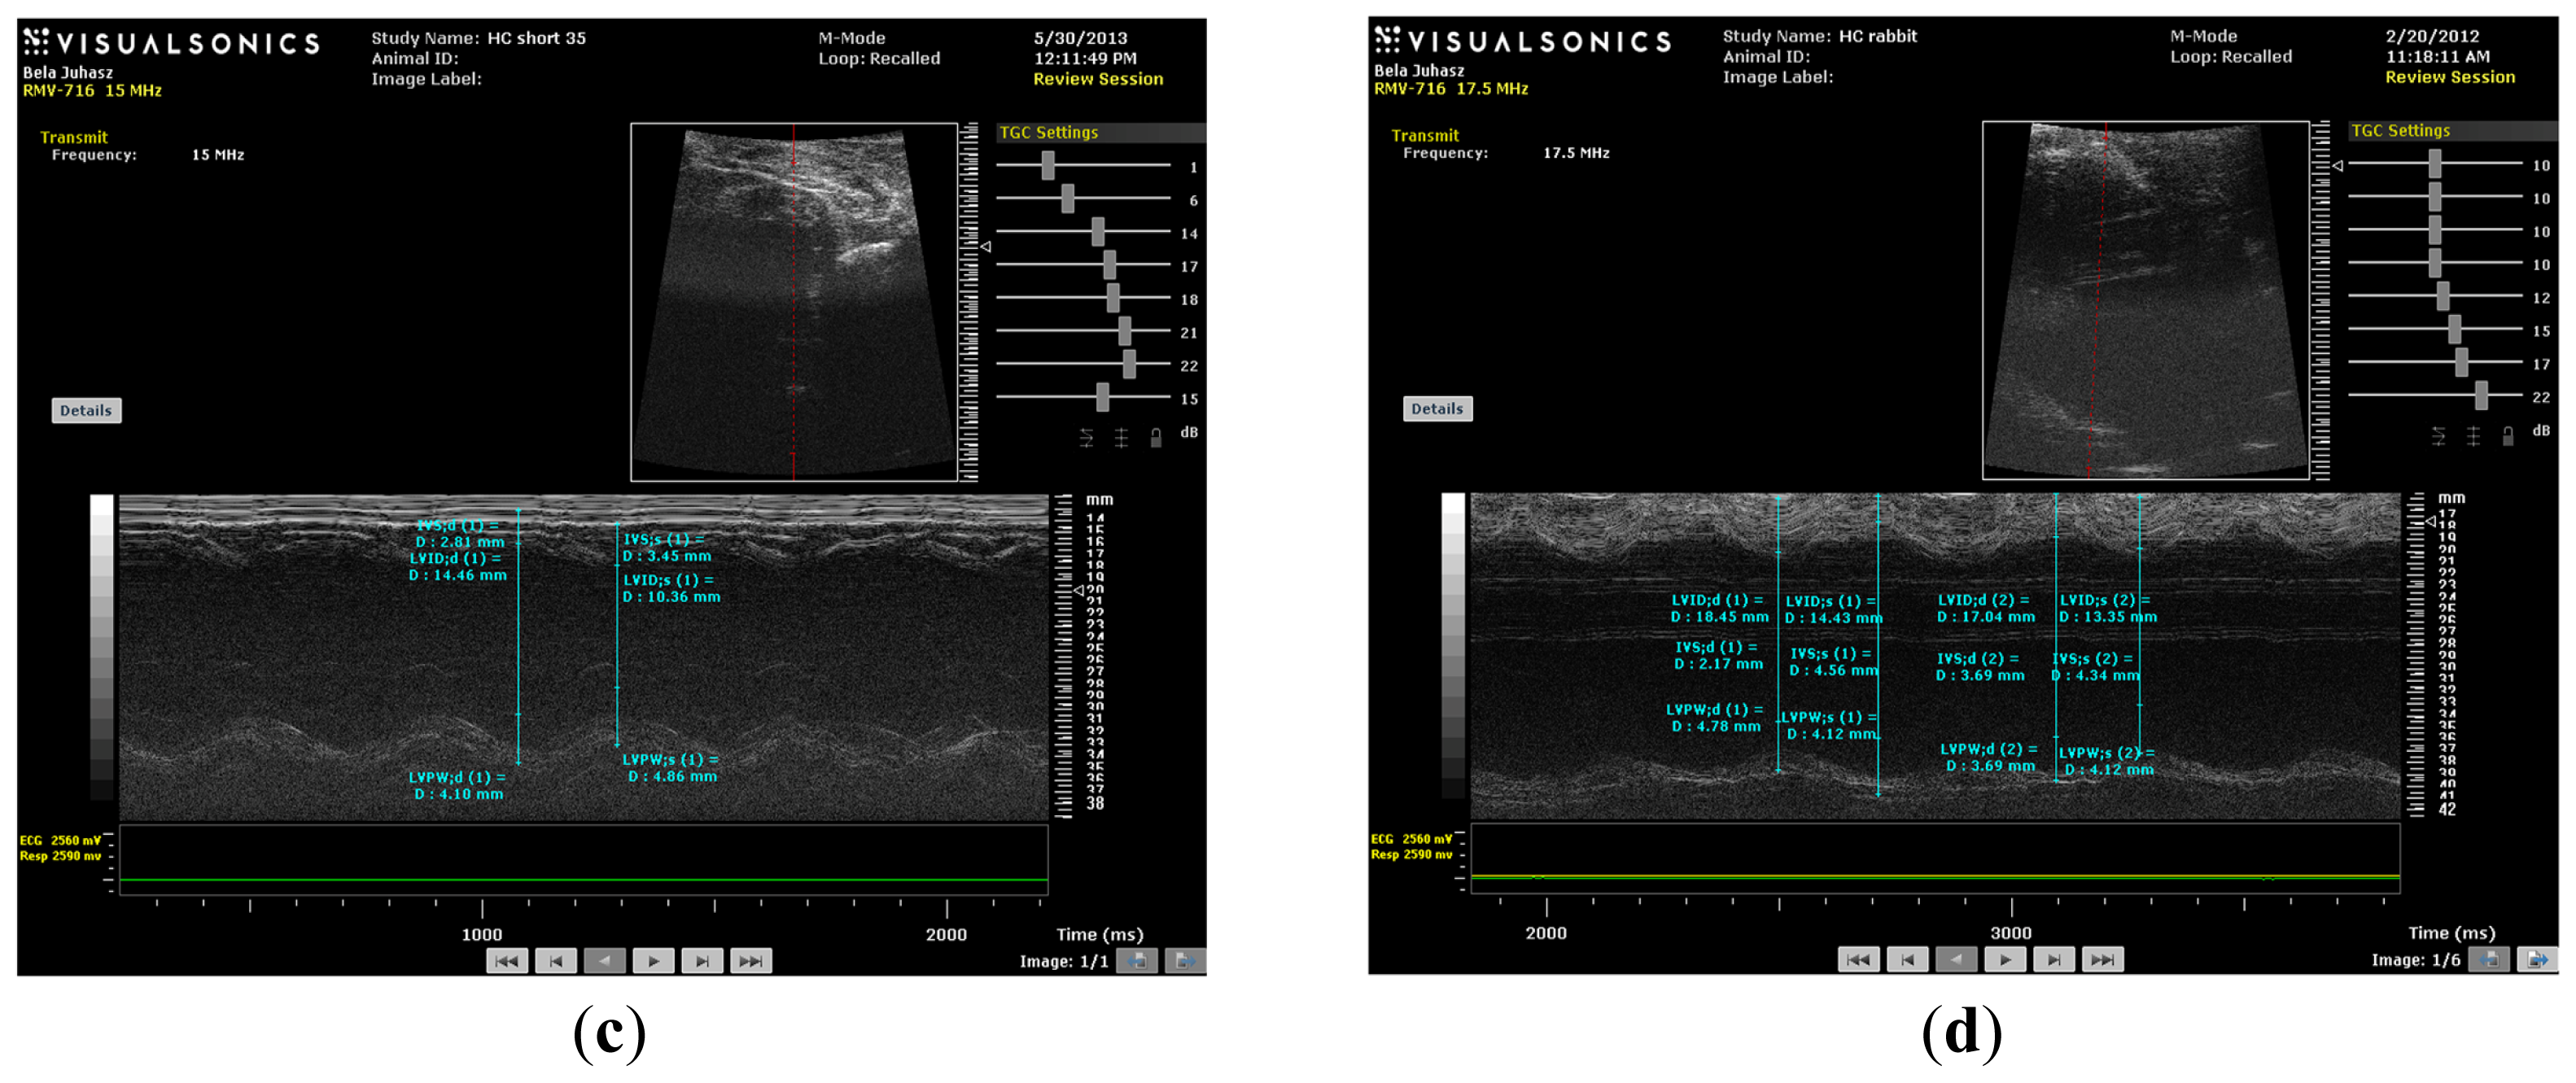

(a) M-mode image of control short (CS) heart; (b) M-mode image of control long (CL) heart; (c) M-mode image of HC short (HCS) heart; (d) M-mode image of HC long (HCL) heart.

M-mode images demonstrate cross-sections of the heart swept by the instrumentation over a defined time period. This evaluation is conducted by placing the cursor line on 2D images at the mid-ventricular level, with the largest diameter in either the parasternal long or parasternal short axis view (on the M-mode pictures at the upper part 2D views with the cursor; at the lower part, the tracing at the cursor line could be seen). This technique, which provides a very high temporal resolution, allows the end systolic [minimal diameters, left ventricular internal diameter at end-systole (LVIDs)] and end diastolic [maximal diameter, left ventricular internal diameter at end-diastole (LVIDd)] diameters to be precisely measured. These parameters are used to calculate fractional shortening [(LVIDd − LVIDs)/LVIDd] and ejection fraction [(LVIDd − LVIDs)2/LVIDd2] (cubed formula), which are indicators of left ventricular emptying capacity. Normally, the heart ejects more than 50% of its end diastolic volume (ejection fraction), and the diameter shortens more than 25% (linear ejection fraction or fractional shortening). When the myocardial tissue is damaged (typically by oxidative stress), its contractile function is attenuated and emptying capability decreased.

As shown in Figures 4 and 5, the values of fractional shortening (FS) and ejection fraction (EF) of the left ventricle were significantly reduced in HC long animals relative to their values in non-hypercholesterolemia control rabbits (p < 0.05) and to animals maintained for shorter time periods on hypercholesterolemia-inducing chow (HC short) (p < 0.05). These outcomes are expected based on previous studies, which reveal significant positive correlation between the occurrence of cardiac insufficiency and associated heart failure with possible left ventricular hypertrophy [22–24]. The aforementioned echocardiographic data provides insight into the influence of high cholesterol on the underlying pathogenesis of cardiovascular disease and helps account for other observations described in the present report, such as increased infarct magnitude in hypercholesterolemia animals. No significant differences in Groups I–III were observed. This expectation shows that neither ageing itself nor short-term hypercholesterolemia afflict the systolic and diastolic parameters and normal heart function. Although, in animals receiving a long-term cholesterol diet, these values were significantly lower (p < 0.05), which shows that long-term hypercholesterolemia can deteriorate left ventricle systolic function. As seen in Table 1, no significant differences in other echocardiographic parameters were measured. It should be also noted that the left ventricle (LV) masses of Groups II and IV were higher than the LV masses of the short-treated animals, although this only represents that the LV mass is correlated with increasing body weight, since these animals were five months older at the moment of extermination.